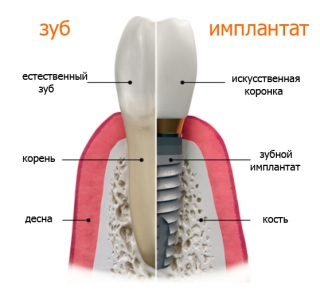

Зубной имплант является искусственным корнем зуба и выполняет функцию опоры для коронки, несъемного мостовидного протеза или крепления любой съемной конструкции.